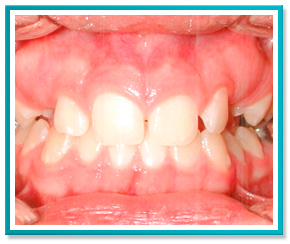

5. PROBLEMAS COM A DENTIÇÃO INFANTIL

Problemas com a dentição de seu filho?

Saiba que quanto antes for a intervenção, mais fácil, rápida e conservadora será a correção.

Veja a seguir as fotos de um caso onde foi necessário trazer para frente o incisivo central que encontrava-se totalmente escondido.

A correção foi feita através de aparelho removível com ação de molas, em menos de 1 ano de tratamento.